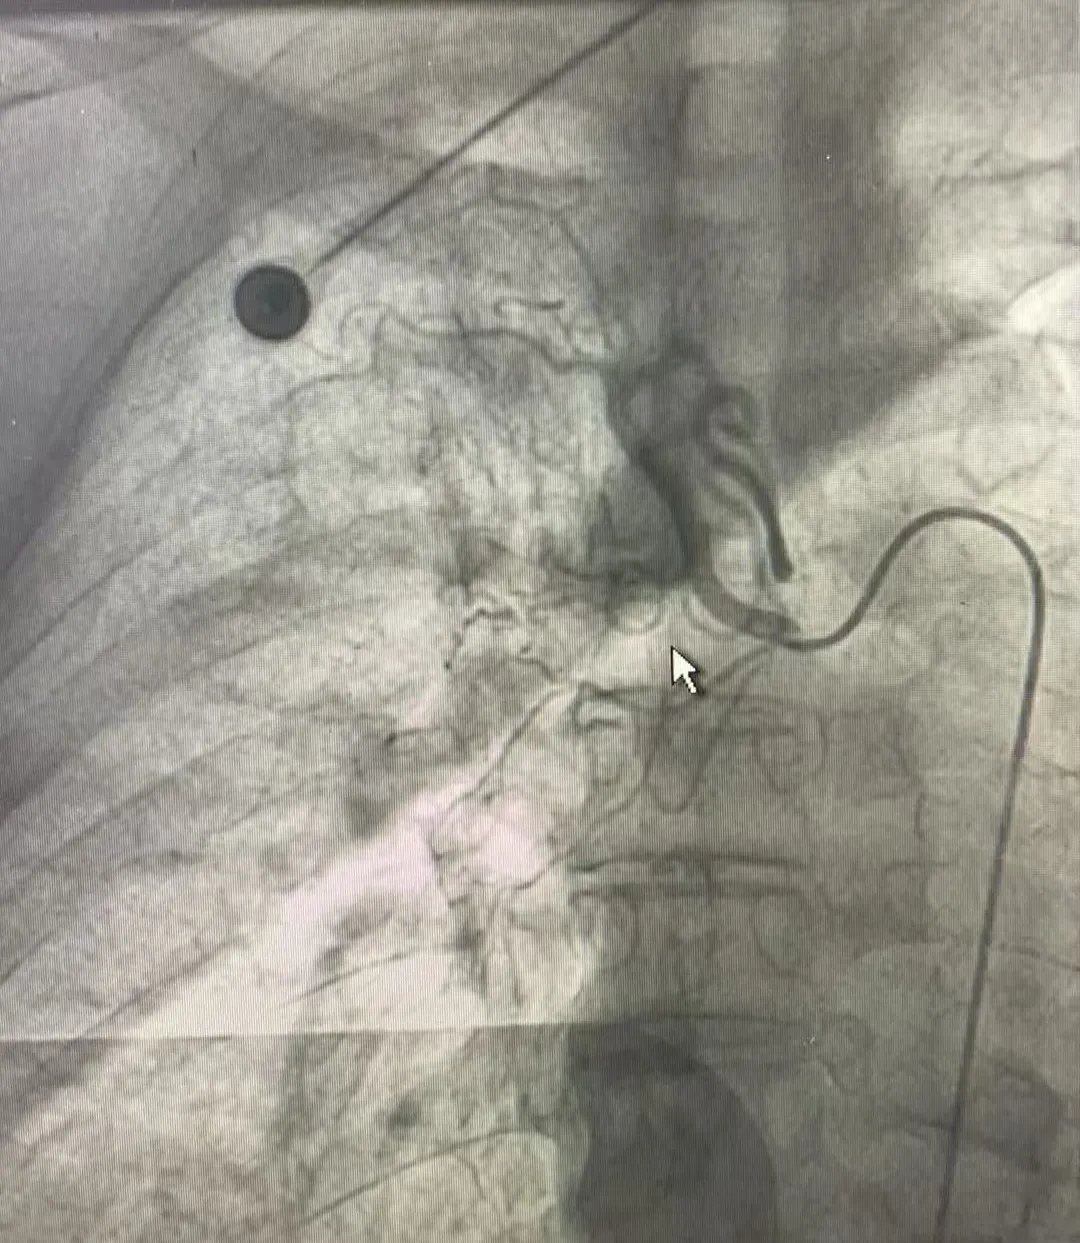

患者雷某因“反复咯血1月,复发5天”入院,入院第5天,患者突发大咯血,病情危重,随时可能发生气道阻塞或失血性休克。经与家属充分沟通并排除手术禁忌后,呼吸与危重症医学科团队迅速为患者施行急诊支气管动脉造影+支气管动脉栓塞术。

手术在局部麻醉下进行,凭借数字减影血管造影设备(DSA)的精准引导,团队快速定位出血的支气管动脉,经微导管注入栓塞材料,成功封堵目标血管。术后造影显示血流显著减缓,栓塞效果良好,手术顺利完成。患者安返病房后,咯血症状明显缓解,术后第二天未再咯血。